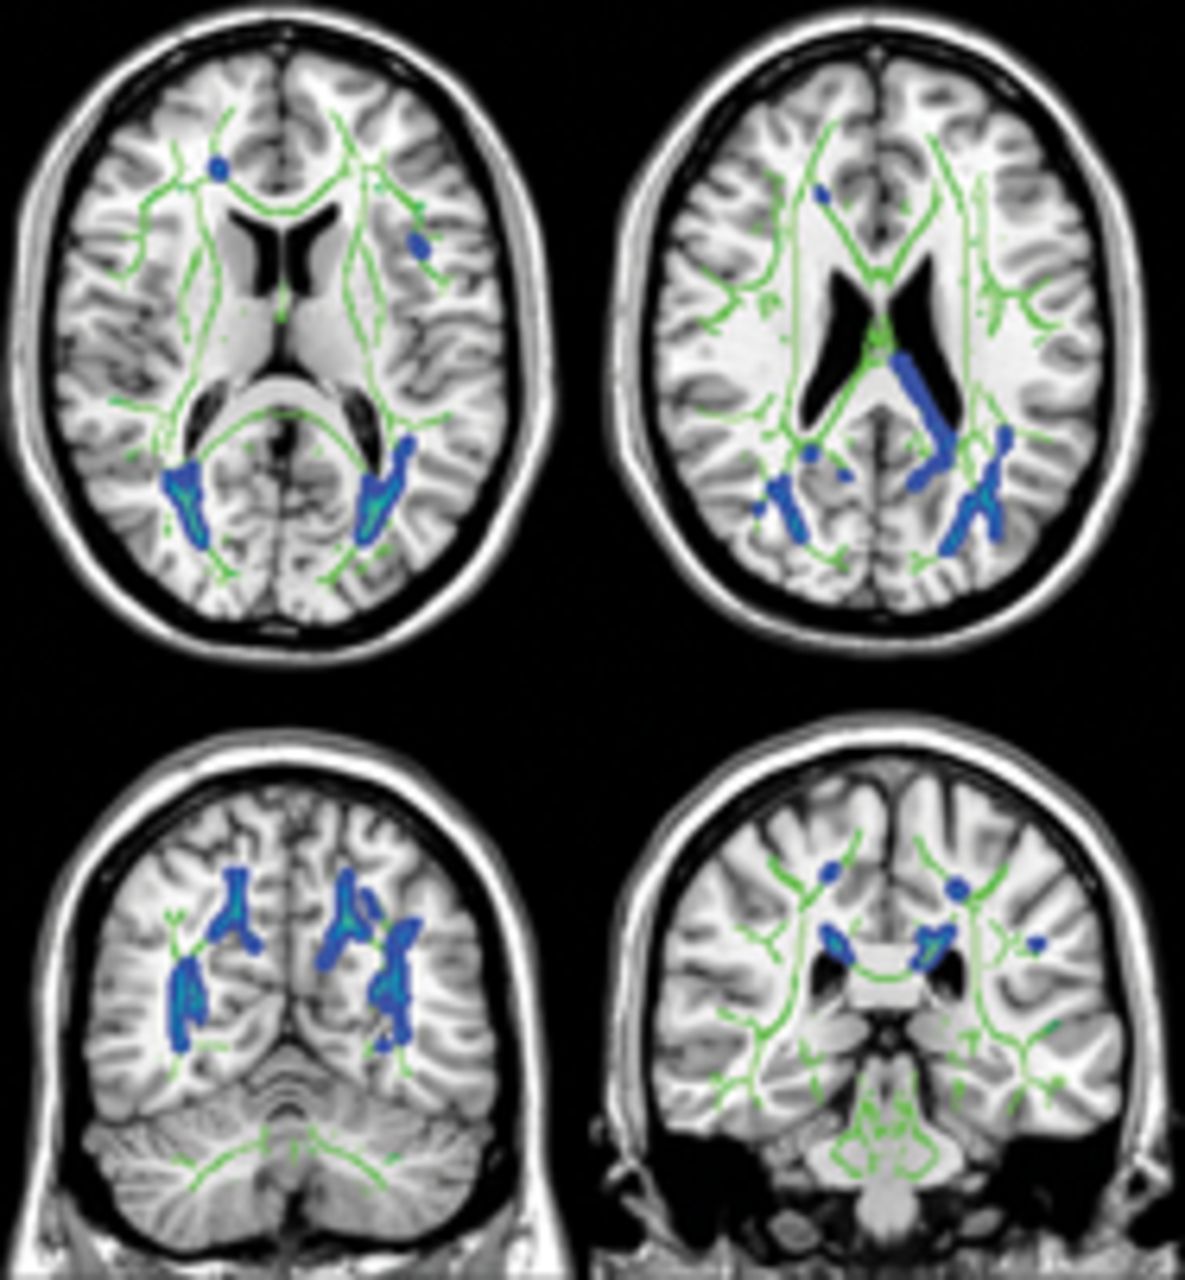

新的缺血性损伤与急性脑出血共存

本研究招收了97名急性高血压脑出血患者(我)诊断3天内发病。Diffusion-weighted和梯度回波T2 *三成像在5天内进行。新的缺血性病变发生的一起我可能是一个有用的标记来识别高危患者未来临床脑血管事件或血管性死亡。

看到p。848年

从作者的普拉巴卡兰& Sheth:“设置急性缺血的证据我已经真正的影响,可能会导致一个新的治疗模式:修改后继发性缺血的风险我为了降低中风复发风险和提高长期的结果。”

看到p。838年